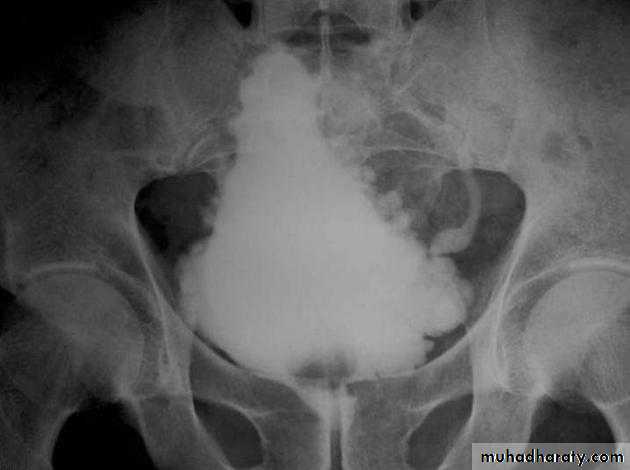

Calcification of the urinary bladder wall

bladder exstrophy

radiographic appearance in bladder exstrophy. It describes wide midline separation of the pubic bones.Bladder exstrophy (also known as ectopia vesicae) refers to a herniation of the urinary bladder through an anterior abdominal wall defect. The severity of these defects is widely variable.